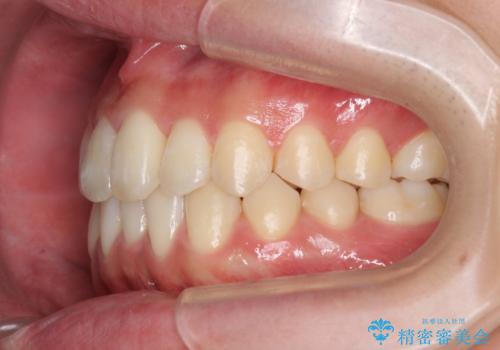

残りは全て天然歯になり、人工物の心配をしなくて済むようになりました。

治療も順調に進み、リファインメントも1回のみで済んでいます。

ブラックトライアングルも少なめで、短期間でしっかり並びました。